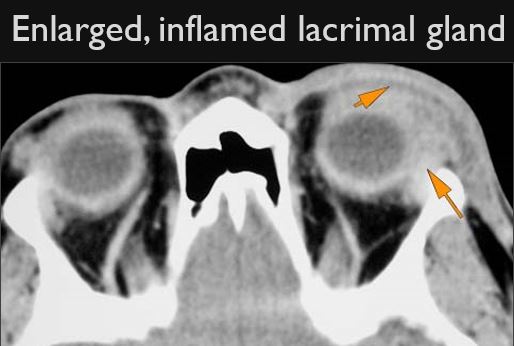

The lacrimal glands are enlarged and/or enhance abnormally.